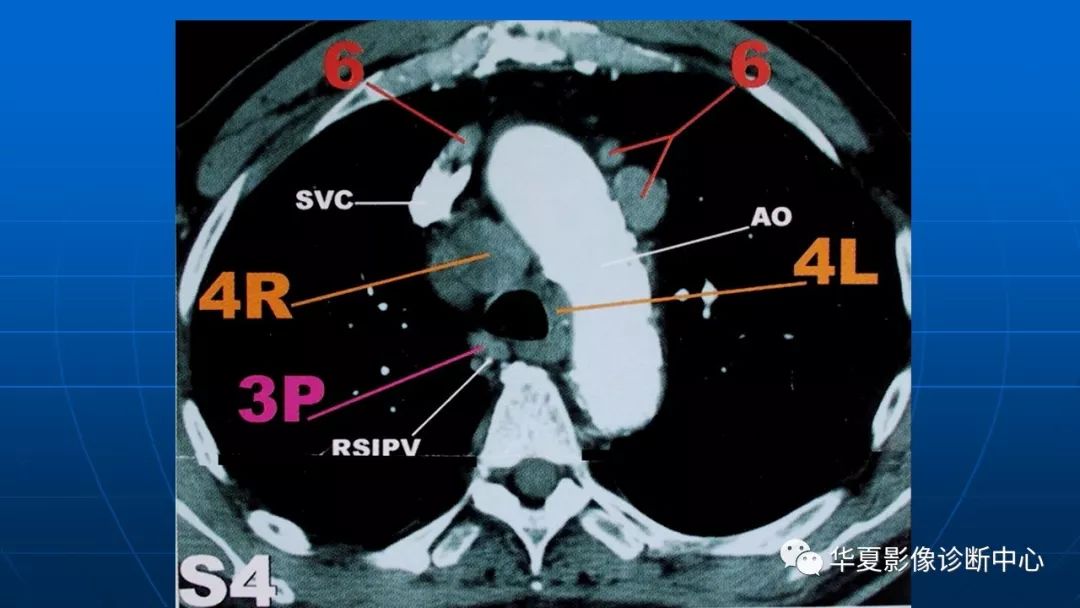

肺癌分期纵隔淋巴转移ct展示